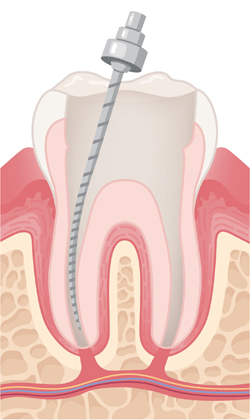

염증이 생긴 신경과 감염된 조직을 제거하고, 뿌리관 내부를 깨끗하게 청소한 뒤 치료에 적합하도록 넓히고 정돈합니다.

잘 소독된 뿌리관 공간을 영구 재료로 빈틈없이 채워 세균이 다시 침투하지 않도록 봉쇄하는 중요한 단계입니다.